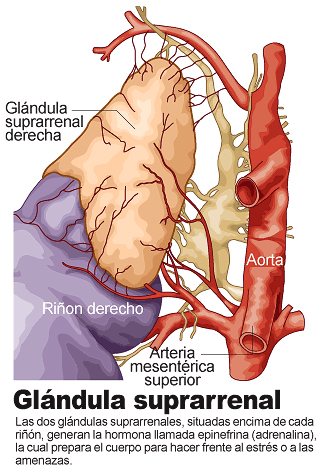

Glándula suprarrenal

Conoce cuántas glándulas suprarrenales tiene el cuerpo.